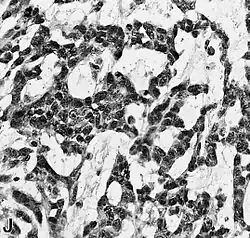

Examen microscópico

El glioblastoma es una neoplasia anaplásica de la glía compuesta por células tumorales astrocíticas pobremente diferenciadas, polimórficas, con marcadas atipias nucleares y una intensa actividad mitótica. Otras características peculiares a fines diagnósticos son también la marcada proliferación microvascular y la presencia de necrosis. Como sugiere el adjetivo "multiforme", la morfología histológica del glioblastoma es extremadamente variable, con células redondeadas, en forma de huso, de dimensiones más bien pequeñas o muy grandes. Mientras que algunos glioblastomas muestran un alto grado de polimorfismo celular y nuclear, con numerosas células gigantes plurinucleadas, otros presentan una conformación caracterizada por una celularidad intensa, pero más bien repetitiva.

La naturaleza astrocítica de la neoplasia puede resultar bastante fácil de identificar, al menos localmente, en algunos tumores, pero difícil de reconocer en otros, debido al alto grado de anaplasia. La heterogeneidad de región a región del glioblastoma es relevante y dificulta el diagnóstico en muestras limitadas, como las obtenidas por biopsia estereotáxica[70] (véase la fotografía en Cirugía). A pesar de la presencia predominante de células poco diferenciadas, en algunos puntos se pueden distinguir astrocitos neoplásicos más diferenciados. Esto es particularmente cierto en los casos de glioblastoma como resultado de la progresión de un astrocitoma difuso (grado II de la escala OMS). La transición entre zonas que aún poseen diferenciación astrocítica reconocible y zonas de alta anaplasia celular puede ser continua o repentina. Un cambio brusco en la morfología refleja habitualmente la aparición de un tumor diferente, fruto de la adquisición de una o más alteraciones genéticas adicionales.[71]

En el contexto de la neoplasia se observan grandes áreas de necrosis, rodeadas de núcleos dispuestos paralelos entre sí, formando "empalizadas" típicas. Se encuentra una marcada proliferación de células endoteliales con formación de numerosos vasos, a veces con apariencia de montón o madeja. Algunos tienen pared hialina y otros están trombosados. La proliferación endotelial, sin embargo, no es difusa sino focalizada en algunos puntos. Alrededor de la neoplasia se pueden encontrar zonas de astrocitos gemistocíticos (astrocitomas difusos de grado II).[11][61]